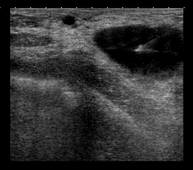

Breast ultrasound

This imaging method uses sound waves create an image of blood vessels, tissues and organs, including the breasts. Ultrasound imaging allows for the evaluation of abnormalities detected by mammography or clinical examination, distinguishing between solid and fluid lesions (cysts).

Ultrasound-guided FNA (fine-needle aspiration)

In fine needle aspiration (FNA), a thin needle is inserted under ultrasound guidance into a suspicious area of the breast; a syringe is then used to extract a small amount of tissue, which is sent for cytological examination. It is also used to puncture and drain breast cysts and analyse their contents. The procedure lasts only a few minutes and causes slight discomfort.

Ultrasound-guided CNB (core-needle biopsy)

A core-needle biopsy or core biopsy involves obtaining a cylinder of tissue for histological study. Under ultrasound guidance and after administering local anaesthesia, the needle is placed in the area to be studied and, using an automatic cutting system, several millimetre-long cylinders of tissue are obtained. It is a relatively short and relatively painless procedure. It allows a significant sample to be obtained for histological study.